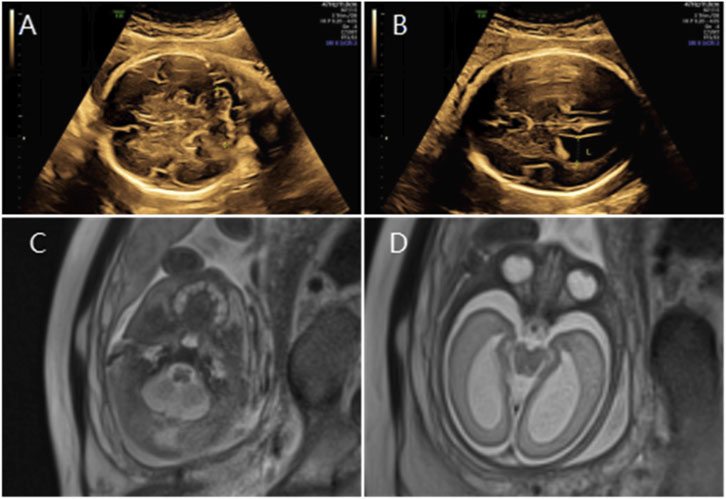

Figure 3

Ultrasound and MRI images are arranged in two rows. The top row shows ultrasound images labeled A and B, depicting a fetus in the womb with varying views. The bottom row displays MRI scans labeled C and D, providing detailed cross-sectional views of the fetus’s anatomy.

Figure 3. (A) Transverse ultrasound section showing the fetal cerebellum; transverse cerebellar diameter measured 24.8 mm (<–3.2 SD for gestational age), consistent with cerebellar hypoplasia. (B) Axial ultrasound view in the transventricular plane demonstrating bilateral ventriculomegaly, with atrial widths of 10.6 mm (left) and 11.2 mm (right). (C,D) Axial T2-weighted fetal MRI confirming cerebellar hypoplasia and bilateral ventriculomegaly.